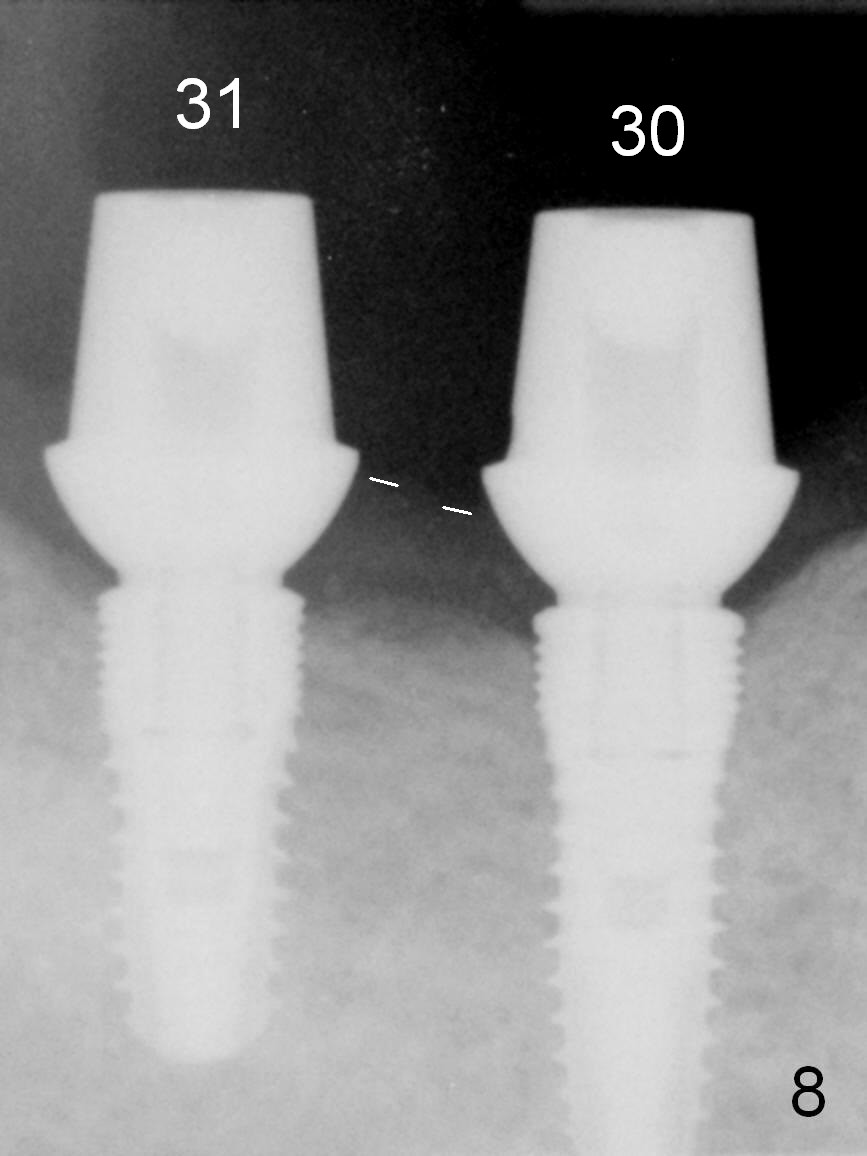

One month later, the patient returns for #30 and 31 implant placement. As planned, the initial depth is 10 and 8 mm (Fig.6). What is unexpected is deficiency in ridge width. Narrower implants (as compared to those on the left) are placed (Fig.7: 4.5x12 and 4.5x10 mm). With shorter implants, the implants are later placed deeper (as shown by arrows in Fig.7) so that almost all of the microthreads are buried in the bone. It is expected that there is less chance of thread exposure postop. The later turns out to be true 3.5 months postop (Fig.8 with 6.8x5(3) mm abutments). It appears that the abutment margin is supragingival (white dashed line: gingival margin) and should be trimmed prior to impression. Or change the abutments to ones with shorter cuff. It may be so for those at #18 and 19 (Fig.9: 4 months postop). Custom full arch trays will be used for impression with bite registration. In fact the mesial margin of #19 abutment is ~ 2 mm subgingival. A longer-cuff abutment is used (6.8x5(3) mm) at #19 before impression.